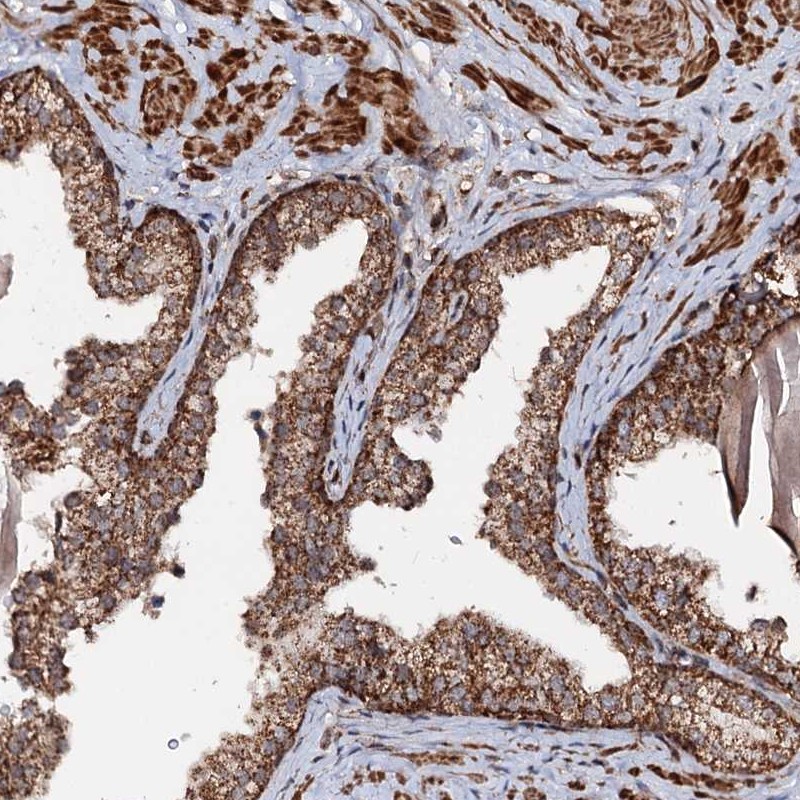

Immunohistochemical staining of human prostate shows strong cytoplasmic positivity in glandular cells.